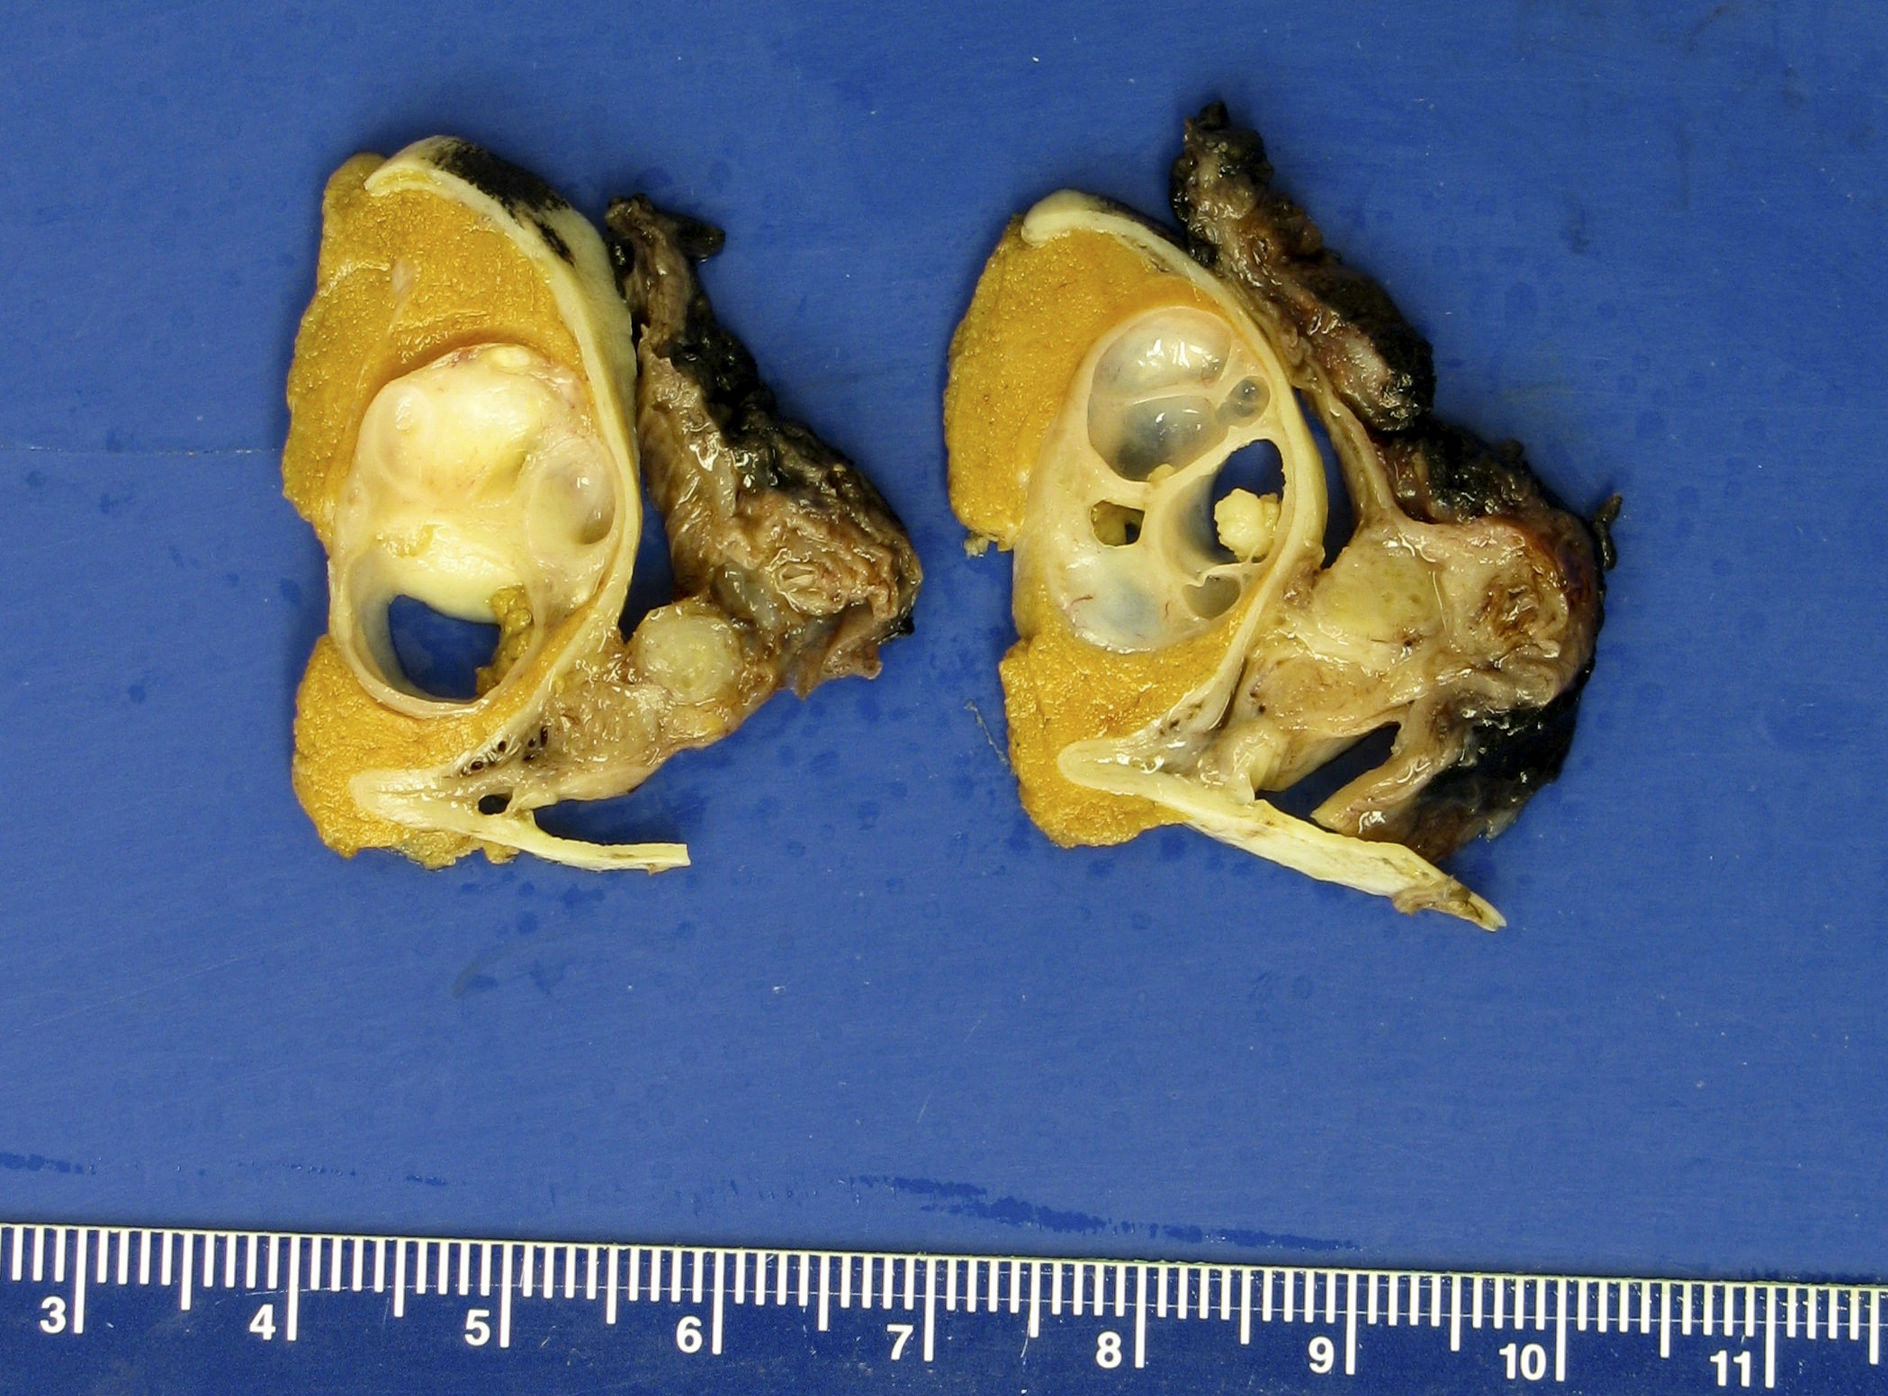

Gross images

Contributed by Debra L. Zynger, M.D.

Complete regression (pT0)

Germ cell neoplasia in situ only (pTis)

Partial regression (pT1)

Teratoma (pT1)

Teratoma and EC (pT1)